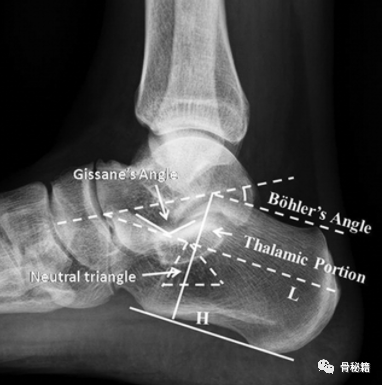

1. 侧位像。在侧位片上有 2 个非常重要的影像学标记

Böhler’s 角:评价跟骨高度和关节压缩情况;

Gissane’s 角:评价跟骨前、中和后关节面的相对位置改变。